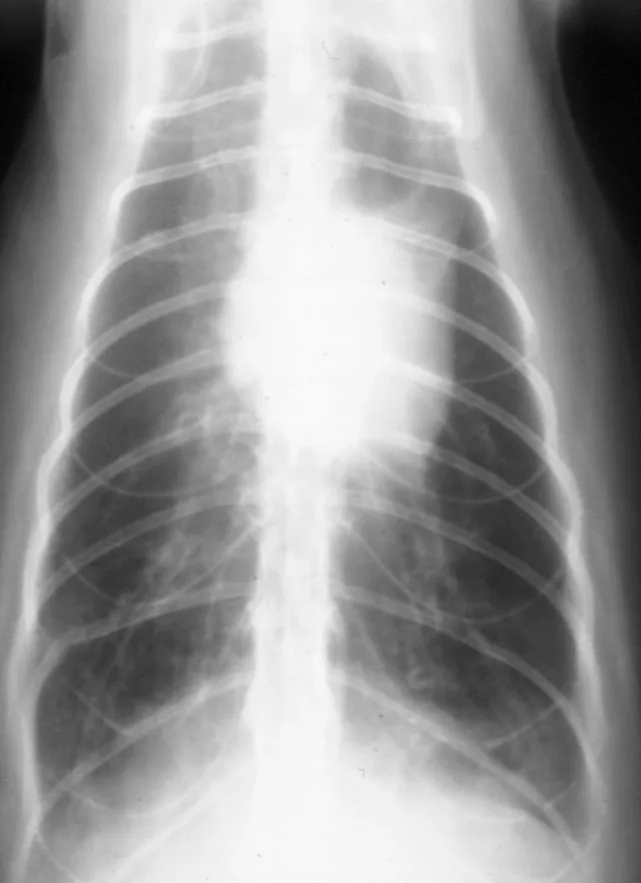

When lower airway tract disease is suspected, good-quality thoracic radiography is essential. Both lateral views and a ventrodorsal (or dorsoventral) view should be obtained. Radiography can confirm and localize disease and also provide information on severity of changes.

Radiographic changes in "asthmatic" cats often include a prominent bronchial pattern (tram lines and donuts) or a mixed pattern of bronchial, alveolar, or interstitial changes. With increasing disease severity or chronicity, atelectasisof the right middle lung lobe or left cranial lobe (caudal segment) and generalized lung overinflation may be evident (Figure 3).

FIGURE 3 Thoracic radiograph of a cat with long-standing disease. A prominent bronchial pattern, general hyperinflation, and atelectasis of the left cranial lobe (caudal segment) are evident.